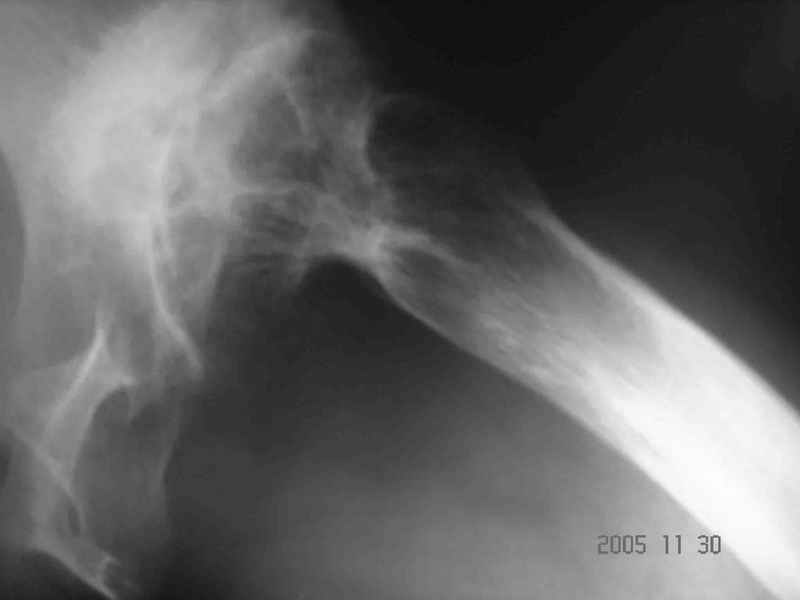

Уважаемые коллеги, прошу дать совет по данному случаю. Пациентка 32 лет с диспластическим левосторонним коксартрозом 3 ст. Из анамнеза - в детстве операции по поводу врожденного вывиха левого бедра (остеотомия таза по Хиари и остеотомия проксимального отдела бедра, аппаратное удлинение голени) В настоящее время беспокоят боли в левом тазобедренном суставе, ограничения движения (сгибание 60 гр, отведение 20 гр, общ ротация 30 гр); укорочение левой н/конечности на 5 см. Пациентка ставит задачу о полноценности тазобедренного сустава и коррекции длины нижней конечности. Р-гр прилагаются. Какой тип эндопротеза оптимален в данном случае? Как проводить коррекцию укорочения? (аппаратное удлинение голени после протезирования?)Буду весьма благодарен за помощь.

Что касается типа протеза, лучше прислать рентгенограмму лучшего качества, на которой вертельная область видна полностью.

Если подходить к заданным Вами вопросам академически, то в обязательном порядке необходима Р-грамма в аксиальной проекции, особенно учитывая перенесенную МВО, т.к. возможны деформации, не видимые на представленных снимках. Если ориентироваться только на то, что Вы прислали, то я не вижу больших проблем с выбором бедренного компонента - обычная ножка клиновидной формы из того ряда что Вы имеете в своем выборе.

Другой и самый сложный вопрос - расположение и фиксация вертлужного компонента. На мой взгляд, оптимальное решение - расположение чашки в анатомическом положении с компенсацией недопокрытия за счет аутокостной пластики (из удаленной головки). Если Вы подниметесь выше (более 2,5-3 см), то велика опасность проваливания в полость малого таза, т.к. предсказать истинную анатомию после перенесенной остеотомии таза про Хиари крайне сложно. Как показывает опыт, после такой остеотомии лучше не верить картинке стандартной Р-граммы, а ориентироваться на анатомическое положение фигуры слезы. Хорошим решением была бы КТ.

Уважаемый Алексей! На наш взгляд пациентке необходимо выполнить бесцементное эндопротезирование. Особое внимание уделить формированию имплантационного ложа чашки протеза -симметрично контрлатеральному суставу. То есть центрировать фрезу в истинную acetabulum, а не во впадину неоартроза. Причем использование небольшого размера (44-46 мм) впадины протеза позволит её надежно закрепить в тазовой кости без какой-либо костной пластики. Если будет выраженный пороз тазовой кости, то следует предусмотреть впадину с цементной фиксацией. Укорочение нивелируется после протезирования. Дополнительно ничего удлинять не надо. Но имеется вальгус коленного сустава, который возможно придется устранять корригирующей надмыщелковой остеотомией.

Аксиальный Р-снимок

Вы вполне можете обойтись стандартной клиновидной ножкой, определенные сложности будут в установке вертлужного компонента. Если есть вопросы, не стесняйтесь, спрашивайте.

Аксиальная рентгенограмма подтверждает, что Вы имеете дело со стандартным случаем диспластического коксартроза. Смею присоединиться к мнениям коллег